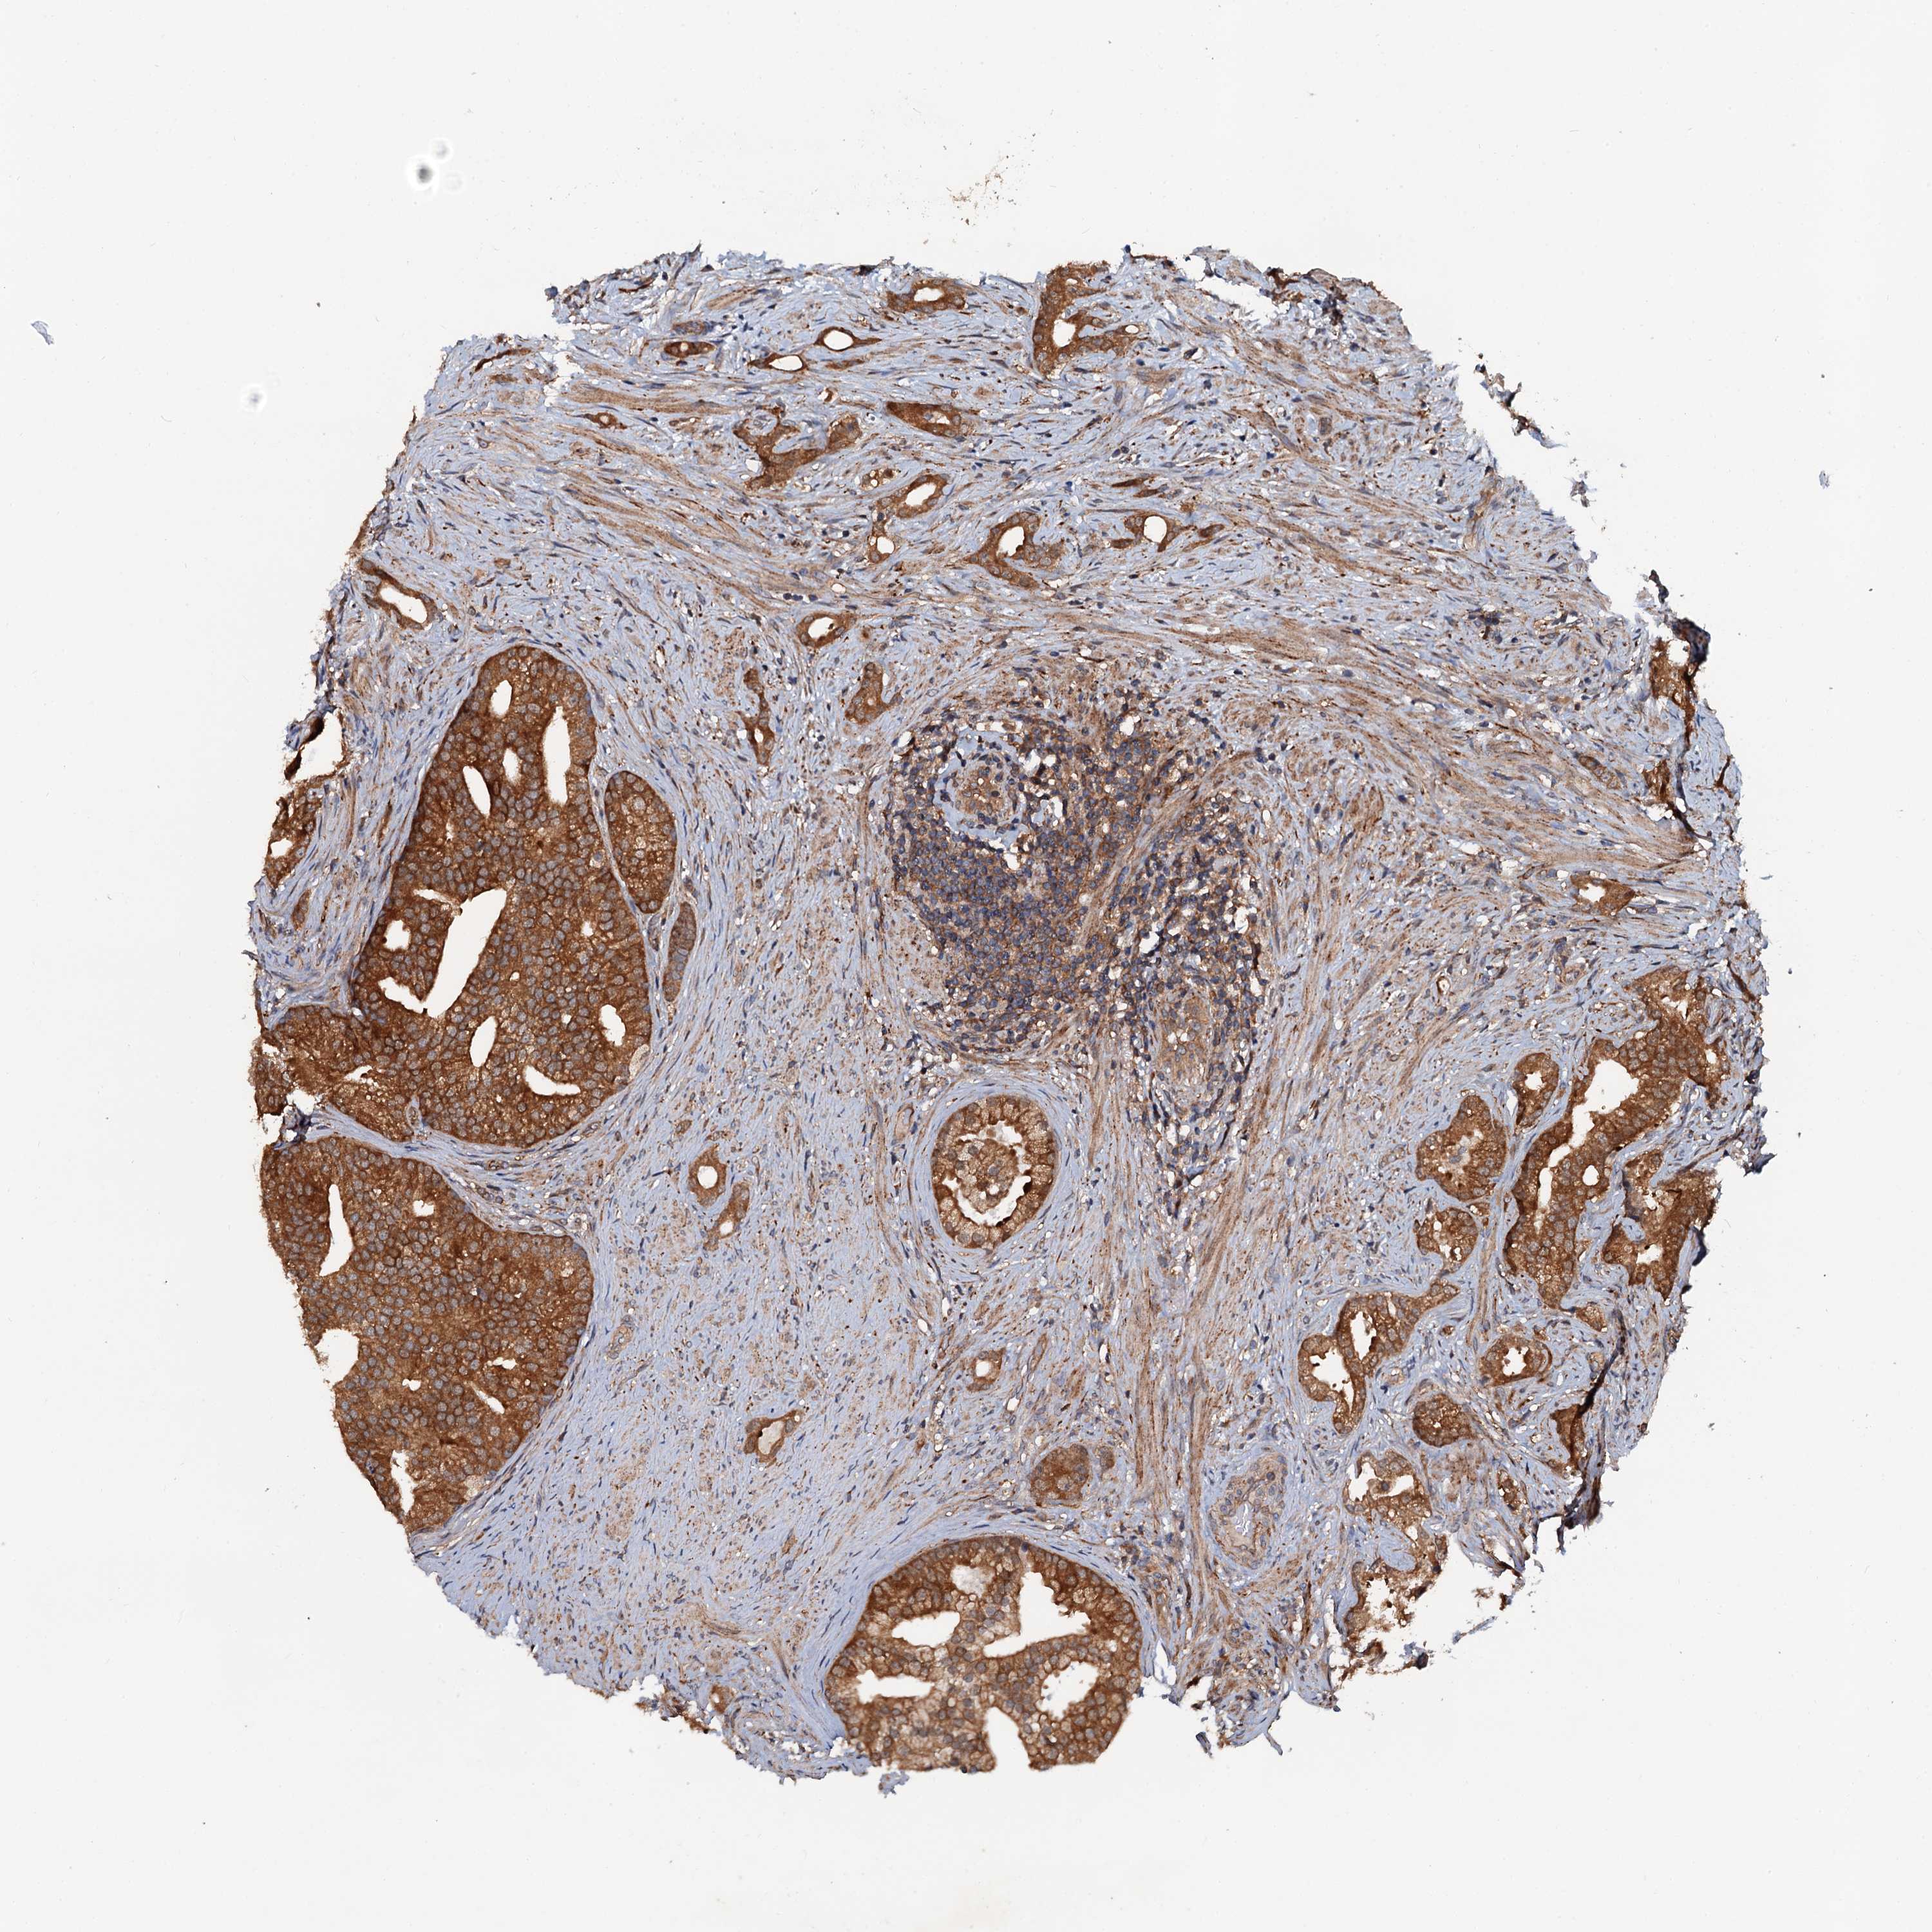

PROSTATE CANCER - Protein expressioni

A mouse-over function shows sample information and annotation data. Click on an image to view it in a full screen mode. Samples can be filtered based on level of antibody staining by selecting one or several of the following categories: high, medium, low and not detected. The assay and annotation is described here.

Note that samples used for immunohistochemistry by the Human Protein Atlas do not correspond to samples in the TCGA dataset.

Antibody stainingi

Antibody staining in the annotated cell types in the current human tissue is reported as not detected, low, medium, or high, based on conventional immunohistochemistry profiling in selected tissues. This score is based on the combination of the staining intensity and fraction of stained cells.

Each image is clickable and will lead to virtual microscopy that enables deeper exploration of all samples and also displays staining intensity scores, fraction scores and subcellular localization as well as patient and tissue information for each sample.

Antibody HPA039371

Antibody HPA040174

Staining

High

Medium

Low

Not detected

Intensity

Strong

Moderate

Weak

Negative

Quantity

>75%

75%-25%

<25%

None

Location

Nuclear

Cytoplasmic/membranous

Cytoplasmic/membranous,nuclear

Adenocarcinoma, NOS

Adenocarcinoma, High grade

Adenocarcinoma, Low grade